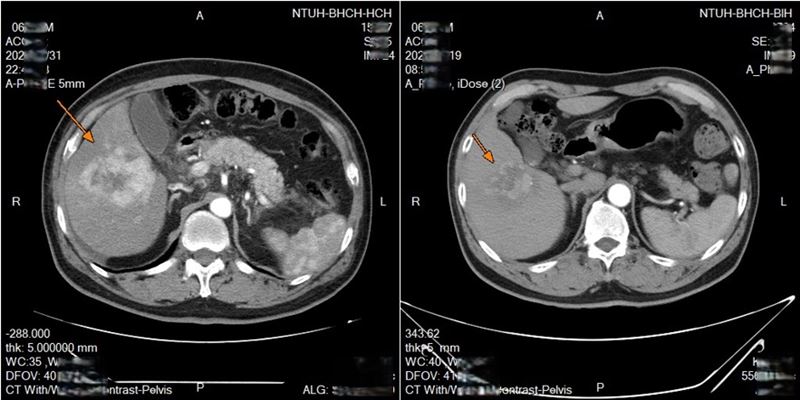

新竹63歲男性,原本罹患淋巴癌,在治療期間又意外發現肝腫瘤,確診肝癌。醫療團隊與病人討論後,採用「鎖骨下導管置放肝動脈灌注化療」技術,歷經兩次療程後,腫瘤明顯縮小,治療效果令人振奮。

這項技術的靈活性更高,每次治療後可重新調整導管位置,若發生堵塞或移位,醫師可立即處理,提升療效並減少併發症。臨床上,許多病人經治療後腫瘤明顯縮小,部分甚至消失,顯示技術潛力十足。